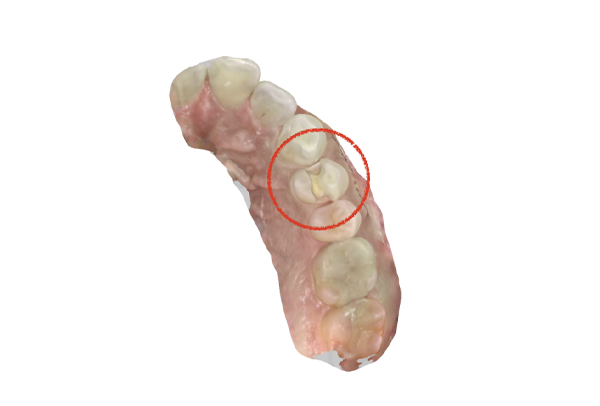

iTero NIRI機能による診査

虫歯除去後

黄色丸の部位が、他の部位と違って白く抜けがあるのがわかります。これがNIRI機能による虫歯の診査です。

この機能のおかげで、歯と歯の間の見つけにくい虫歯がよくわかるようになってきました。

IOSのNIRI機能によって虫歯部分が明らかになったので、虫歯を除去後に修復治療を行うこととしました。

虫歯の有無を確認する上で今まではレントゲンと自分の目での確認でした。現在は目で見るよりもはるかにわかりやすいIOSという装置がありますので、虫歯の発見がしやすくなりました。

そのため、患者さんの虫歯の進行の段階が早いうちにわかる様になり、神経をとらなければならないというケースが非常に少なくなっています。